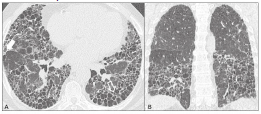

Paciente do sexo masculino, de 65 anos, procura atendimento médico por dispneia progressiva há oito anos até pequenos esforços. mMRC 3, associado com edema de membros inferiores bilateral, e tosse seca esporádica. Nega tabagismo. Nega contato com fogão a lenha. Nega criação de aves. Nega contato com mofo. Trabalha durante toda a vida em vendas de utensílios domésticos. Exame físico: saturação periférica de oxigênio: 88%. Bom estado geral, baqueteamento digital, ausculta pulmonar com estertores finos bibasais, edema em membros inferiores bilateral e simétricos 2+/6+, sem sinais de empastamento das panturrilhas. Sem outras alterações. Traz resultados de exames. Exames laboratoriais: sorologia HIV negativa, hepatite B e C negativas, FAN não reagente, FR negativo. Ecocardiograma: fração de ejeção 65%, PSAP (pressão sistólica de artéria pulmonar) 45 mmHg, aumento das câmaras direitas com disfunção sistólica de ventrículo direito, sinais indiretos com alta probabilidade de hipertensão pulmonar, sem alterações em câmaras esquerdas. Cintilografia de perfusão pulmonar: baixa probabilidade de embolia pulmonar. Espirometria: distúrbio ventilatório restritivo acentuado. Tomografia de tórax: opacidades reticulares finas, com bronquiectasias e bronquioloectasias de tração e cistos de faveolamento, padrão de distribuição predominantemente periférico e basal.